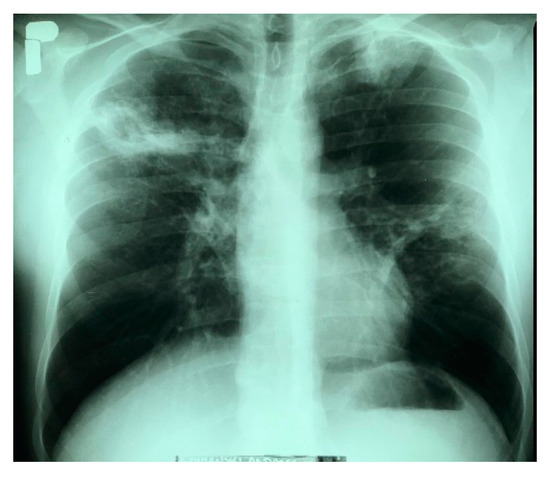

3.1. Human Case